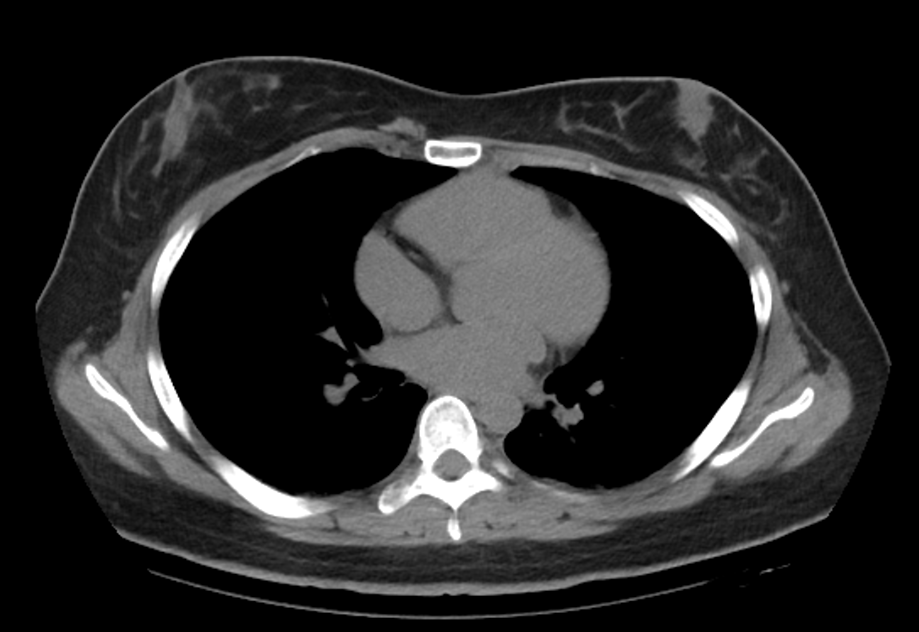

巨乳には乳腺型と脂肪型があるってポストが流れてきたけどそれぞれの参考画像がないとなんとも…… 参考画像がないとなんとも……!

You have both, but some just have more glandular (parts that make milk) than fat. If I squeeze and feel dense parts, that’s the glandulartissue, but if I squeeze and it is soft/plush, that is fat.